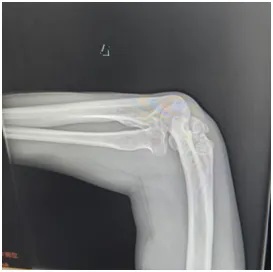

同时,刘师傅的右肘关节也出现了问题——不仅伸屈活动不灵活,外观还明显向外侧撇,正常人的肘关节本身会有一点生理性外翻(女性约10~15°,男性约5~10°左右),可医生测量后发现,刘师傅的肘关节外翻角度竟然达到了30°左右,远远超出了正常范围!

X线显示:肘关节存在明显畸形改变;